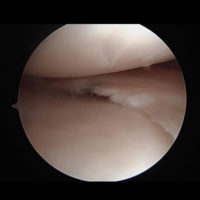

肩関節唇形成術(反復性肩関節脱臼)

関節鏡で肩関節の中を確認し、細い処置具や糸の着いたアンカーを使って、剥がれた骨や関節唇(靱帯)を元の状態に修復します。